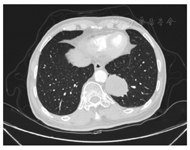

患者男,79岁,于2018年1月2日因"咳嗽5天"收入吉林大学第一医院。患者曾于2013年12月9日因"左上腹不适"就诊于吉林省肿瘤医院,正电子发射计算机断层显像(positron emission tomography computed tomography,PET-CT)提示:左腹部见双发巨大软组织肿物影,彼此相连,上部最大截面10.6 cm×12.7 cm,肿物与大弯侧胃壁界限不清,胃受压移位,局部与肝左叶界限不清,下部与前腹部界限不清;左肺上叶、右肺下叶可见结节影,氟代脱氧葡萄糖代谢无异常。行腹部肿物穿刺活检,2013年12月16日病理诊断提示:梭形细胞肿瘤,形态符合间质瘤;免疫组织化学结果为CD117(+)、Dog-1(-)、CD34(-),确诊为胃肠道间质瘤(gastrointestinal stromal tumor,GIST)。因患者高龄且瘤体较大,瘤体与周围组织分界不清,手术切除困难,遂口服分子靶向药物伊马替尼(400 mg/d)治疗。口服伊马替尼11个月后,2014年11月于吉林省肿瘤医院再次复查全腹部CT示:胃体部大弯侧见肿块,大小约为5.2 cm×6.0 cm,肿块较前缩小且未见转移,临床评估为部分缓解(partial response,PR),伊马替尼治疗有效,继续口服药物治疗。2015年6月因瘤体破裂,于吉林省肿瘤医院急诊开腹行瘤体切除术,此后每3个月复查1次全腹CT,期间患者病情平稳,未见肿瘤进展。2017年12月28日,患者因"咳嗽"于当地医院发现左肺部下叶占位性病变,为行进一步诊治就诊于吉林大学第一医院,2018年1月3日行肺部多排CT二期增强提示:左肺下叶见分叶状高密度影,约4.8 cm×4.4 cm,邻近胸膜受牵拉,见图1。其余部位未见占位性病变,遂行CT引导下左肺下叶穿刺术及病理活检,并行穿刺组织分子病理检测。2018年1月14日病理诊断示:左肺下叶间叶源性肿瘤(图2);免疫组织化学结果示:Ki-67(+40%),CD117(-),Dog-1(+),CD34(+)(图3)。结合病史及免疫组织化学结果考虑为GIST肺转移。2018年1月19日分子病理检查结果:检测到c-kit基因第11外显子发生点突变。综上诊断为GIST术后、左肺转移。追问病史,患者告知近半年,因恶心、呕吐等伊马替尼不良反应,自行调整药物剂量为400 mg隔日一次。综合患者病情,伊马替尼加量至600 mg/d,规律随访,目前已随访6个月,复查2次CT均未见进展或复发。